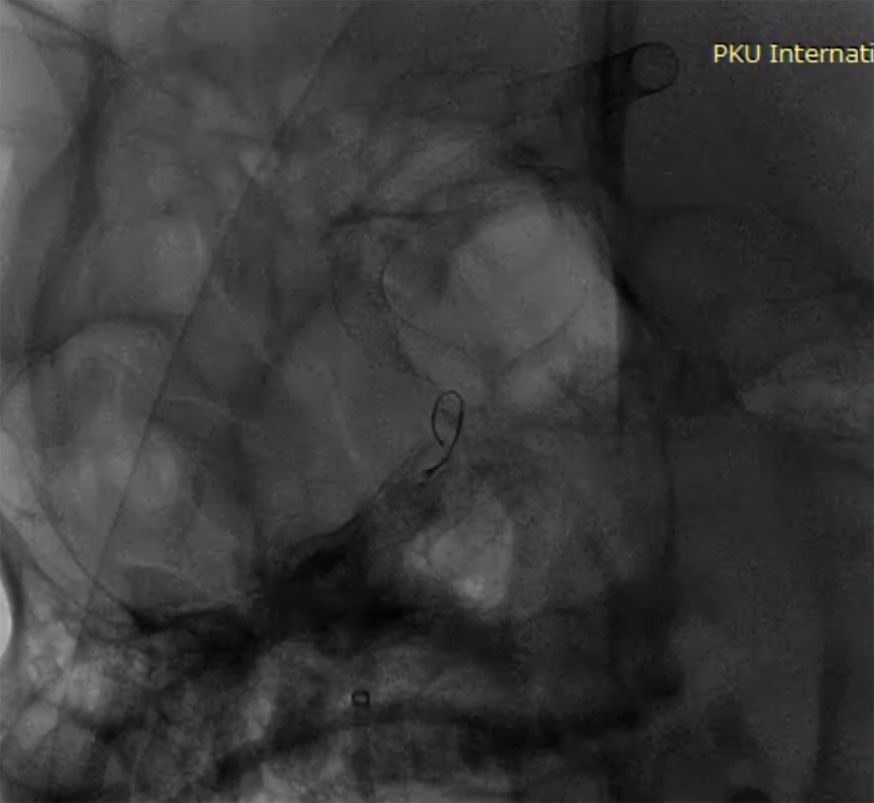

术前造影:

(1)右侧颈内动脉海绵窦段至颈内动脉末端巨大夹层动脉瘤伴血栓形成(图1)。

图1